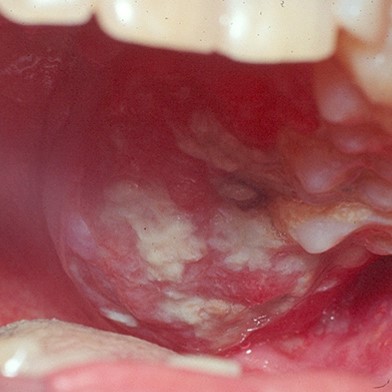

Oral carcinogenesis is a multifactorial process involving numerous genetic events that alter normal functions of oncogenes and tumour suppressor genes.

Together with the loss of tumour suppressor activity, these changes lead to a cell phenotype that can increase cell proliferation, with loss of cell cohesion, and infiltration of adjacent tissue thus causing distant metastasis. Molecular pathology is responsible for defining the molecular mechanisms that underlie the onset of oral precancer and cancer.

The aim of this review is to describe recent advances in our understanding of the molecular control of the innumerable pathways related to these processes. These may lead to short- or medium term improvements in the diagnosis and prognosis of oral precancerous and cancerous lesions and to the development of novel therapeutic approaches to this disease.